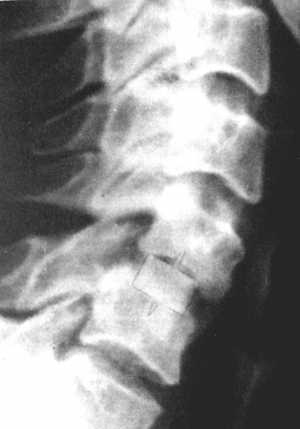

Рис. 3.5: а - травматический вывих С5-С6 позвонков;

б - межтеловая стабилизации металлическим цилиндром сразу после операции;

в - через 3 года после операции. |